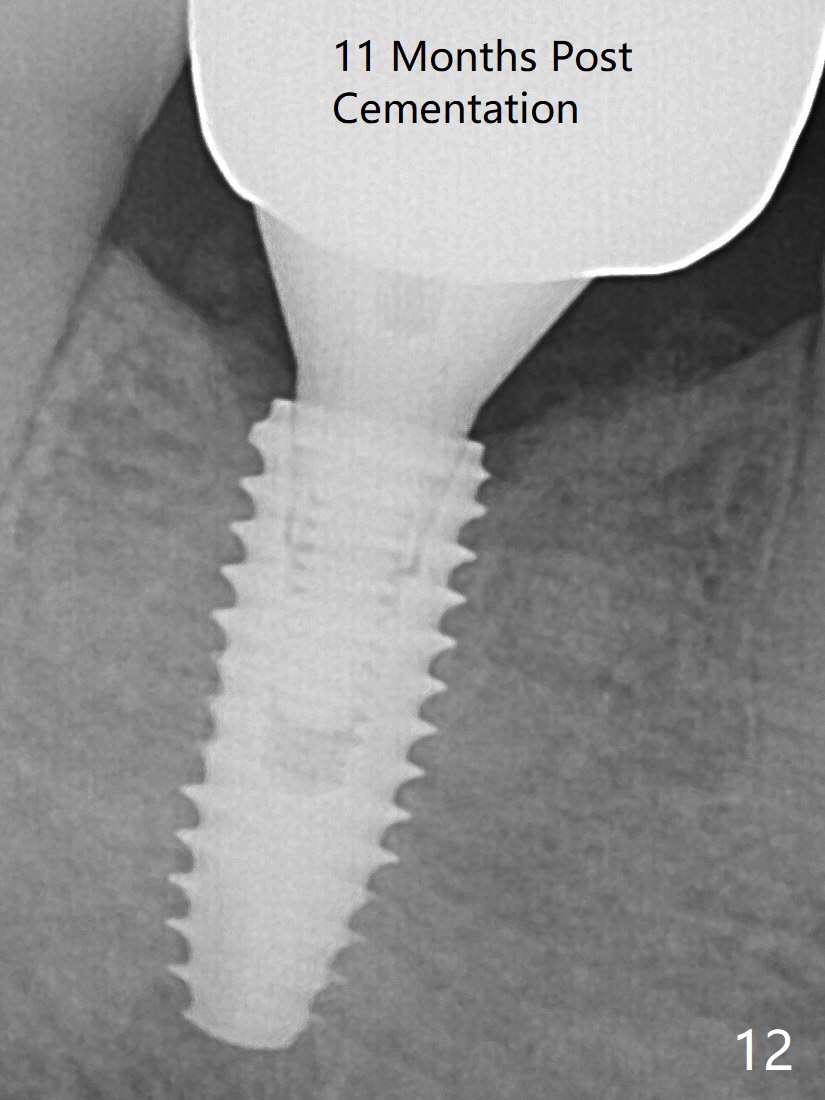

When a definitive implant (Fig.4: 4.5x11.5 mm( *: bone graft)) is placed with primary stability, there is an apical space (Fig.5 white double arrows). There is moderate postop pain. A shorter implant (10 mm) should be tried when the bone is dense. It will be associated with less pain. The fistula disappears 7 days postop (Fig.6). Although the patient appreciates that the pain is gone, there is atrophy mesiobuccally 2 months postop (Fig.7 *). The implant seems to be have been placed too buccally (Fig.8). With loss of the buccal plate, the implant should be placed away from it to prevent periimplantitis. The abutment is changed from 6.5x4(4) to 6.5x5.5 (3) mm with fabrication of a new provisional. The buccal margin is still supragingival 6 months postop and prep lower before impression (to reduce food impaction). The mesial and distal sockets appear to have healed (Fig.9). The bone density around the implant increases 11 months post cementation (Fig.12).